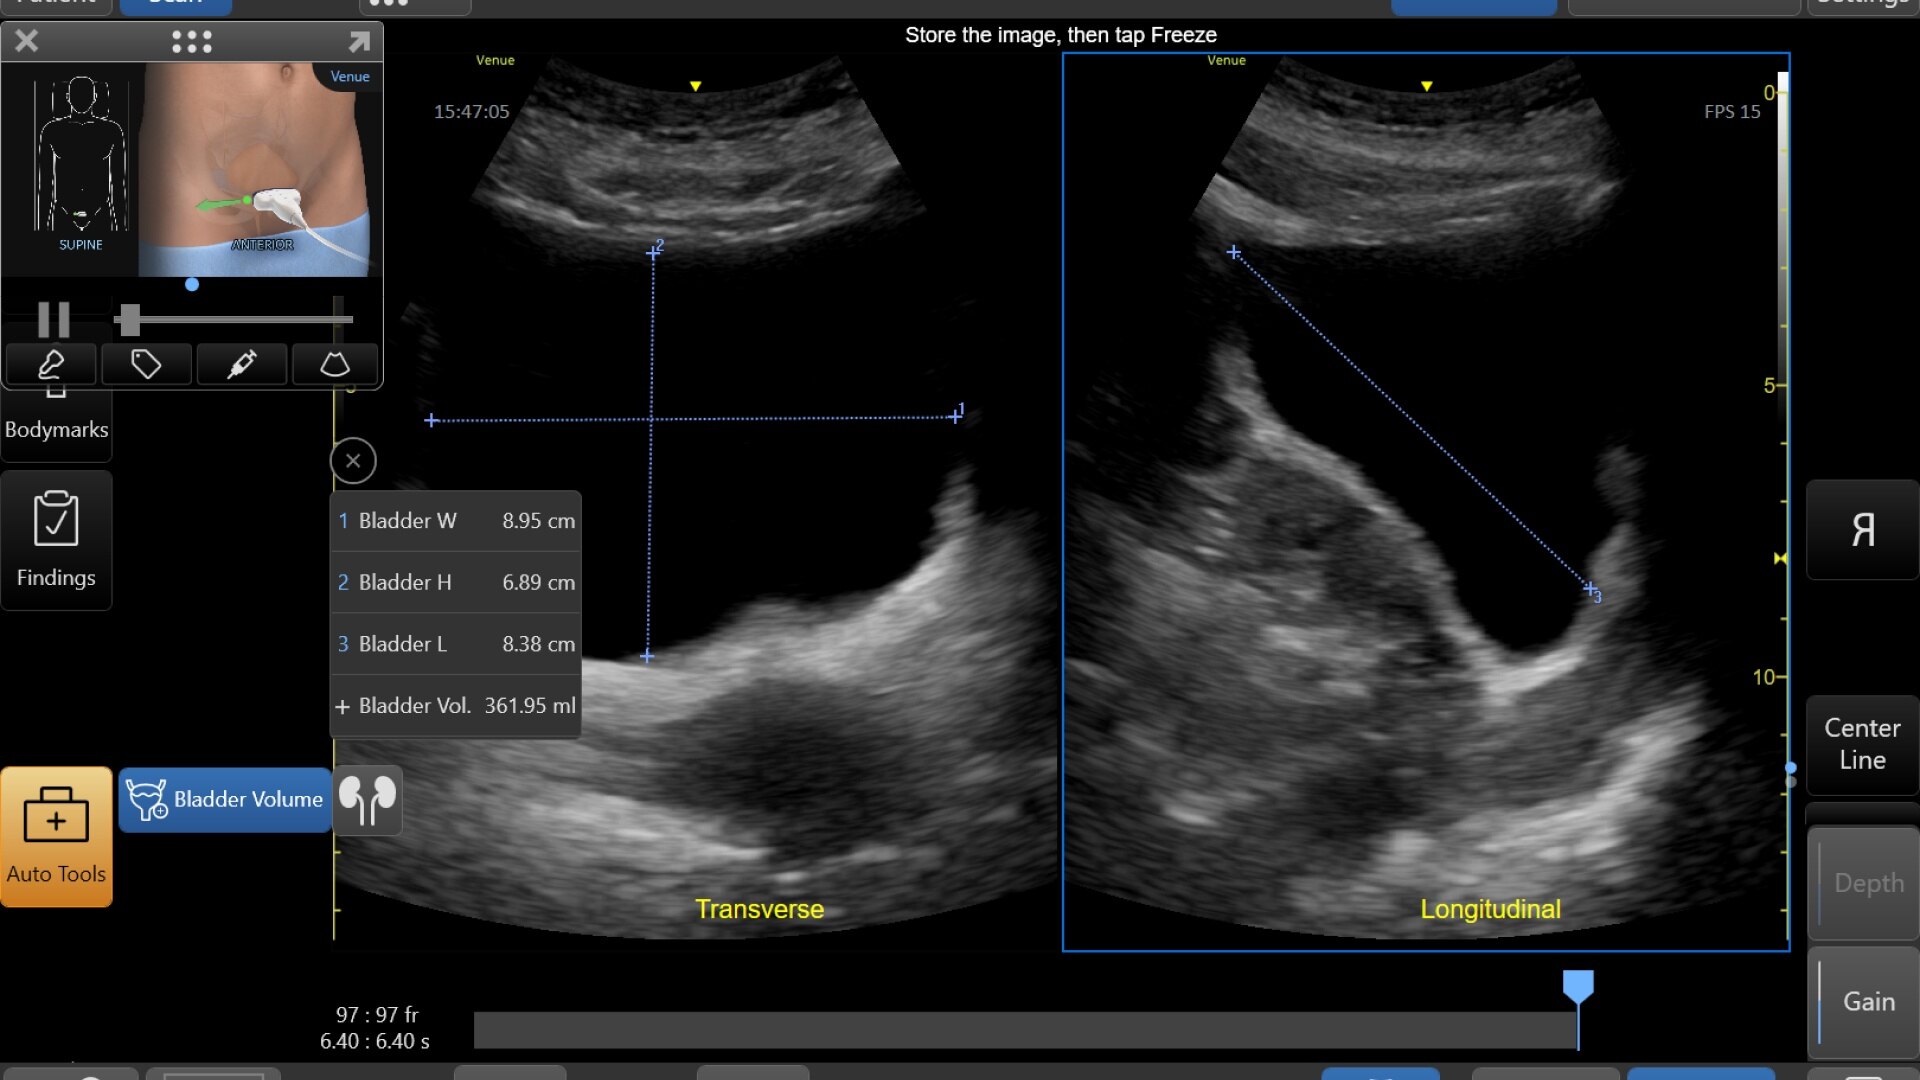

Quick and easy bladder volume documentation

The Bladder Volume Tool is a simplified workflow tool featuring reference images as guidance and supports clinicians in calculation of the bladder volume. The tool is designed to guide bladder volume measurements to make it simple and fast.